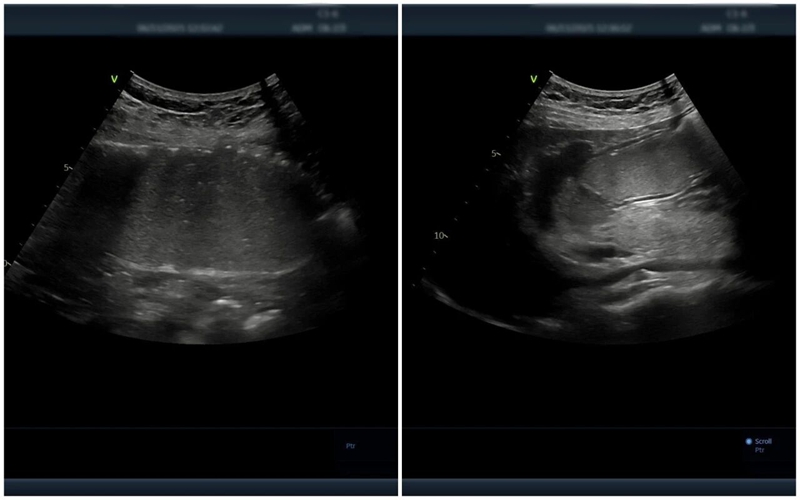

△胃腸超聲造影提示:黏膜層毛糙,回聲減低,胃壁呈局限性增厚,符合慢性胃炎聲像圖特征

簡單來說,就是患者在空腹8小時后,喝下一杯香甜順滑、形似“糊糊”的胃腸超聲造影劑,以此充盈胃腔和十二指腸,有效排除胃腸道內(nèi)的氣體,形成優(yōu)良的“透聲窗”。隨后,超聲醫(yī)師通過超聲設(shè)備,可清晰觀察到胃壁和腸壁的層次結(jié)構(gòu)、厚度變化、蠕動狀態(tài)以及周圍毗鄰臟器的情況,就像給胃腸道做了一次“B超”,輕松便捷。